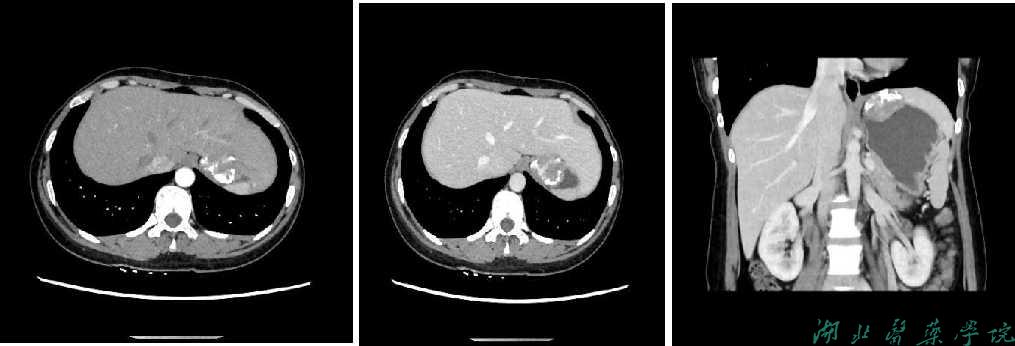

上腹部增强CT示:肝胃间隙内见团块状软组织密度灶,边界尚清,大小约4.1×3.5×3.2cm,病灶内见较多斑片状、环状钙化,增强病灶实性部分呈不均匀渐进性强化,邻近胃壁受压内陷,与邻近肝实质分界欠清诊断:肝胃间隙肿瘤性病变,胃来源?胃间质瘤可能。胃镜下表现为粘膜充血、水肿,散在出血点,诊断为慢性浅表性胃炎。

图1 a)腹部CT增强动脉期;b)门静脉期;c)门静脉期冠状位;d)门静脉期矢状位,可见肝胃间隙软组织密度肿块,肿块边缘钙化,增强呈不均匀渐进性强化。

辅助检查:CT作为一种无创检查的方式,在诊断肿瘤方面具有许多不可替代的优势:它不仅能清晰显示病变位置,还能准确评价病变与周围组织或器官的关系;本病例肿块主要是呈外生性生长,向胃壁外生长,胃镜无法观察到胃壁向外生长的肿块,CT检查可以从横断面观察胃壁外生性肿块的位置,弥补了这一缺陷,此时CT检查便起到了重要的作用。CFT的特征性表现包括位于肿瘤中央或周围分布的钙化灶,表现为粗大的条状钙化或散在的沙粒样钙化,常常单发,边界清晰,增强扫描呈渐近性轻度至中度强化,增强前后CT特征主要根据胃CFT中梭形细胞、胶原、钙化、纤维成分和淋巴浆细胞炎性浸润的比例来确定。

胃CFT是一种罕见的间叶源性良性肿瘤,发病机制尚不明确,多发生于儿童与青少年之中,其中女性稍多于男性,临床表现不典型,常有腹部不适等表现,在影像表现上有一定的特殊性,常呈椭圆形或圆形,常单发,钙化常见,增强呈渐近性强化,边界清晰,对临床诊断起到提示性的作用,最终的确诊还需依靠病理学检查。当CT提示胃肿块并伴钙化时,我们应考虑到此病。